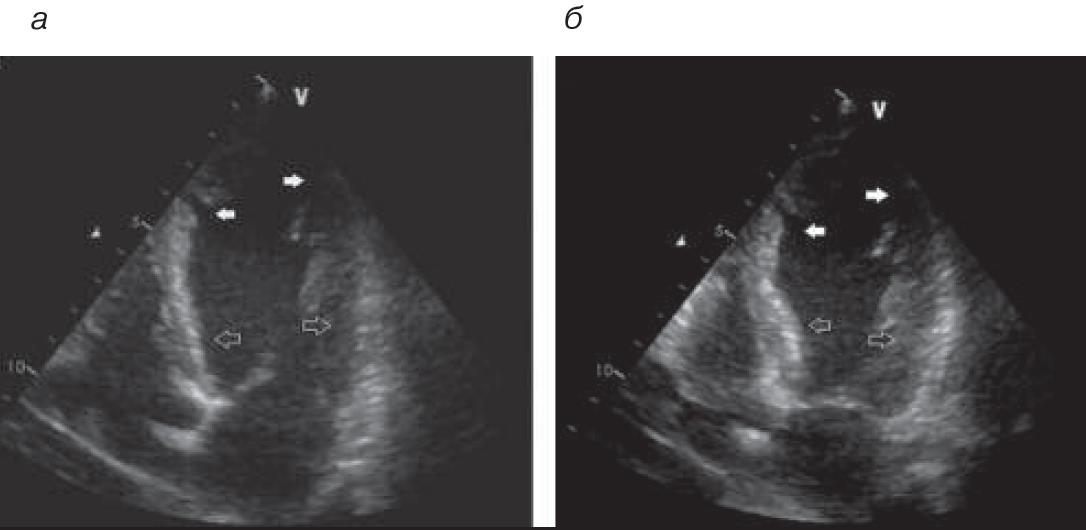

Результаты эхокардиографии (ЭхоКГ) на 2-е сутки: миокард желудочков не утолщен (толщина стенок по 7 мм). Гиперкинезия базальных сегментов всех стенок ЛЖ, выраженная гипокинезия срединных сегментов, акинезия верхушки ЛЖ (рис. 3). ФВ, рассчитанная методом Симпсона, – 45%. Отмечается избыточная трабекулярность миокарда ЛЖ, нельзя исключить некомпактный миокард ЛЖ. Клапанный аппарат без значимых изменений (см. рис. 3).

Рис. 3. ЭхоКГ на 2-е сутки из апикального доступа, левый желудочек: а – диастола; б – систола. Белые стрелки – зоны гипокинезии срединных сегментов.

При повторной ЭхоКГ на 14-е сутки заболевания отмечено: ФВ 60,5%, небольшая гипокинезия срединного и переднеперегородочного сегментов, верхушки ЛЖ. От уровня срединных сегментов к верхушке, передней и боковой стенкам ЛЖ сохраняется избыточная трабекулярность. В области верхушки слой компактного миокарда истончен до 5 мм. Толщина некомпактного слоя 18 мм, соотношение некомпактного и компактного слоев 3,6 (рис. 5).

Рис. 5. ЭхоКГ на 14-е сутки.